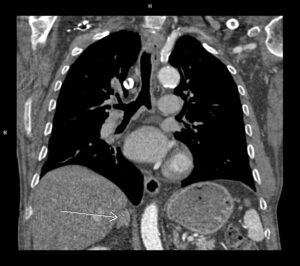

Video 1: reconstrucție oblic sagitală din achiziție angioCT cu sincronizare ECG; săgețile indică soluția de continuitate la nivelul septului interatrial cu circulația contrastului dinspre atriul stâng spre atriul drept

Discuţie caz nr 54 : la nivelul septului interatrial în mod normal există foramen ovale care, dacă este patent, poate permite trecerea contrastului din atriul stâng în atriul drept în cantitate mică. Punerea în evidență la examinarea CT a circulației substanței de contrast dinspre atriul stâng spre atriul drept sugerează necesitatea completării cu ecografie transesofagiană pentru interogarea septului interatrial dar și evaluarea cavităților cardiace drepte precum si interogarea existenței unui eventual drenaj venos pulmonar aberant. Măsurătorile efectuate sunt utile în planificarea închiderii DSA.